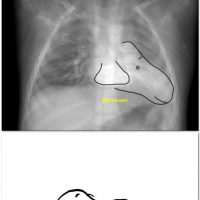

01 year TOF with pericardial agenesis CT: signs of pericardial agenesis 1) Extreme levocardia. 2) Interposed lung between AO&PA. Thick coronal-reformatted average (mean) projection (X-ray like) >>snoopy sign. [gallery ids="17355,17358,17361,17364"]..